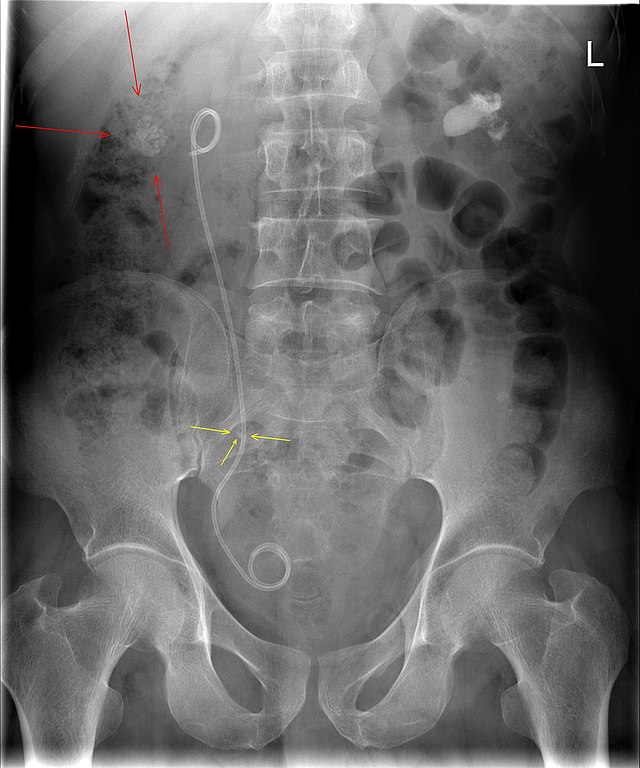

Изображения КТ конкрементов мочевого пузыря